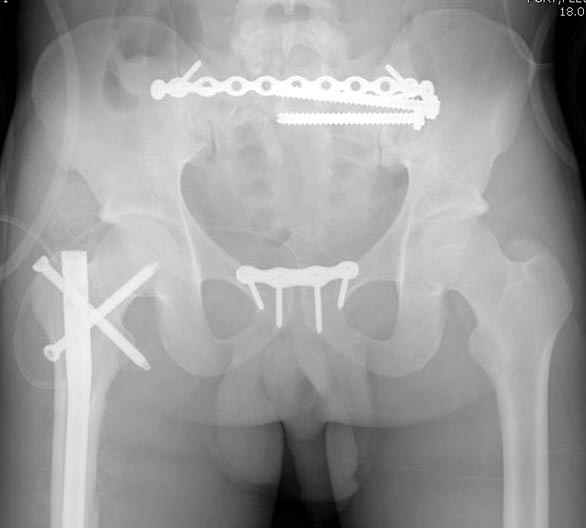

Здесь слайды случая больного с политравмой, включающей сегментарный перелом бедра и повреждение таза с нарушением тазового кольца, разрыв симфиза и перелома крестца зон 2 и 3.

На множественных слайдах важные моменты операции. Хотел бы подчеркнуть, как важно иметь возможности всех необходимых ренгенограмм, включая компютерную томографию и стандартных внутритазовых рентгенограмм (инлет и оутлет).

Djoldas Kuldjanov, MD

Department of Orthopedic Surgery

St. Louis University Medical Center